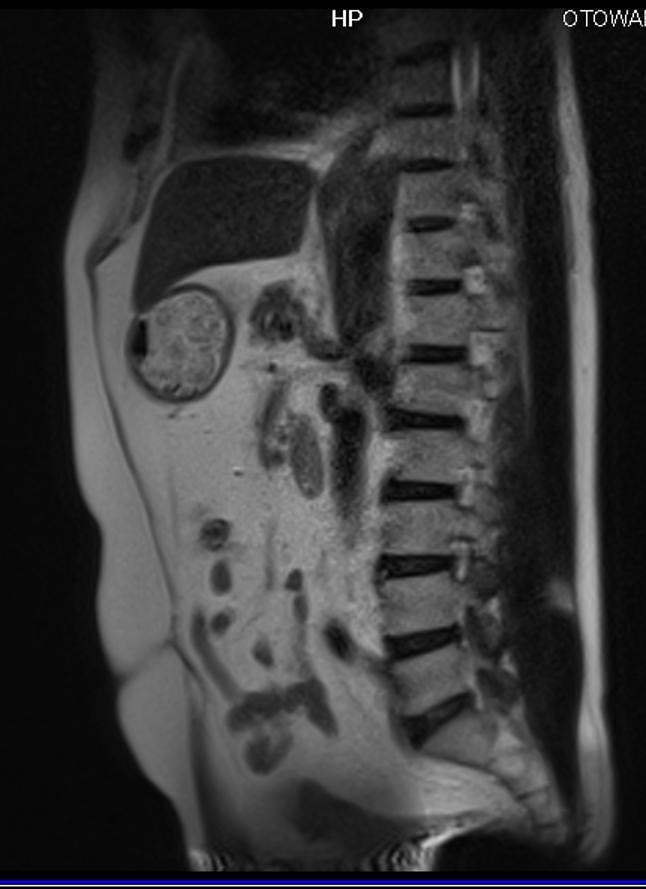

ふくらはぎ痛いとおもったら

MRI検査で腰椎椎間板ヘルニアと判明